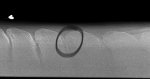

X-ray below- have circled the one which is very tight.

X-ray below- have circled the one which is very tight.